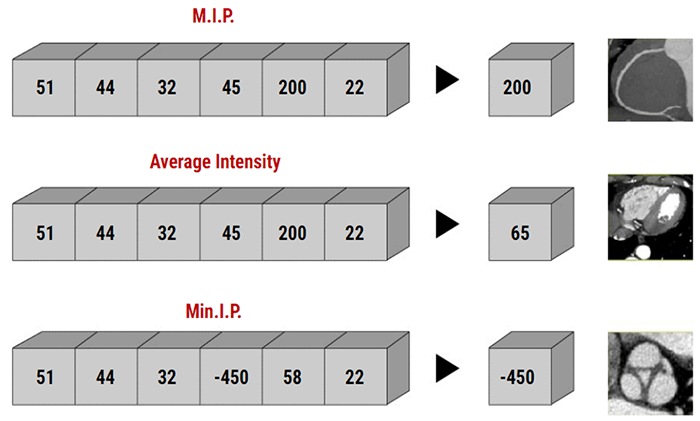

There are three main methods, the minimum intensity projection, the average intensity projection, and the maximum intensity projection.

Maximum Intensity Projection: MIP

The maximum intensity projection consists of projecting the voxel with the highest attenuation value on every view throughout the volume onto a 2D image. An image that displays the maximum intensity for each pixel point on a thickened reformat plane.

Minimum Intensity Projection: MinIP

The Minimum Intensity projection is a data visualization method that enables the detection of low-density structures in a given volume.

Average

In the average intensity algorithm (AIP), the visualization is averaged. The AIP technique is an algorithm that is intended to create a thick MPR image by using the average of the attenuation through the tissues of interest to calculate the pixel viewed on the computer.